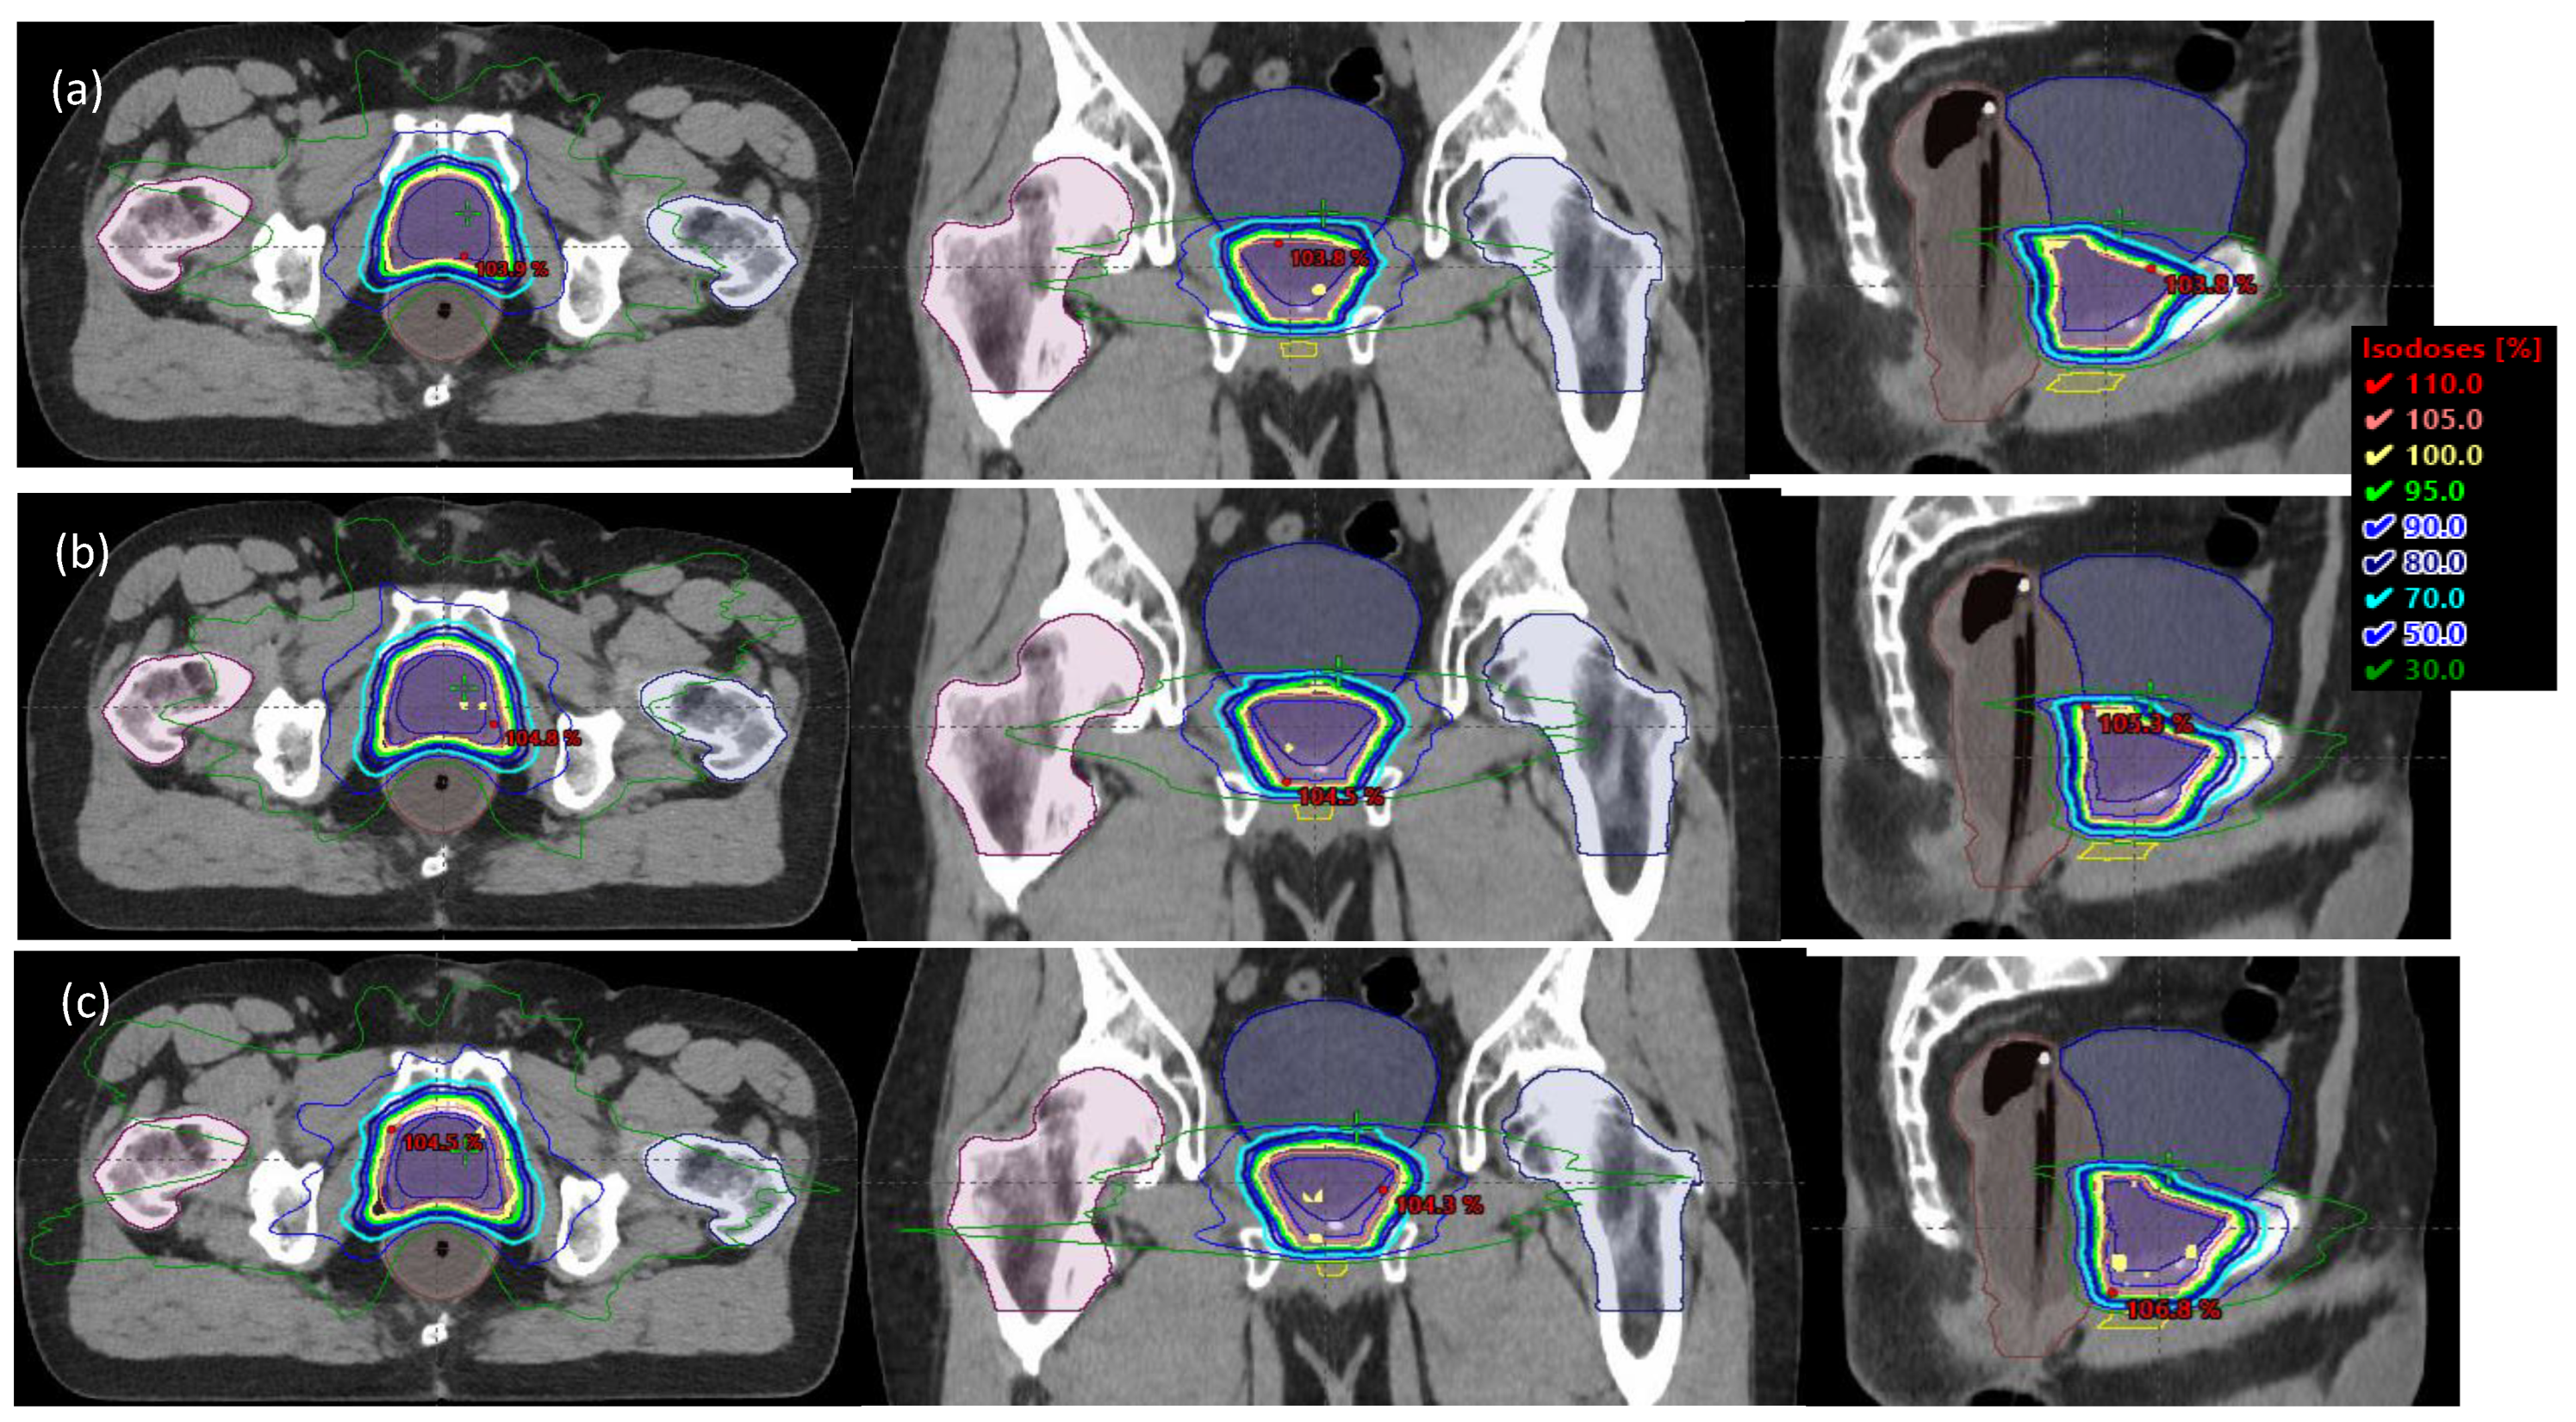

2.1. Patient Characteristics, Simulation, and Planning

2.2. Data Acquisition and Analysis

3. Results